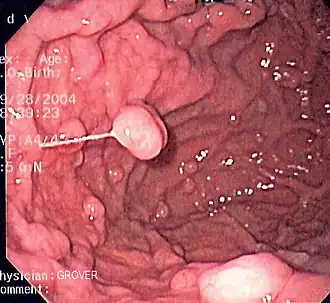

Гастроинтестинальная эндоскопия

Эндоскопические исследования выполняются с помощью специальных аппаратов-эндоскопов, вводимых пациенту через естественные отверстия — рот или задний проход и передающих изображение в исследуемом органе или на окуляр эндоскопа или на монитор. В современной практике используются два типа гибких эндоскопов: волоконно-оптические фиброэндоскопы и видеоэндоскопы, оцифровывающие видимую в объектив картинку и передающие её в таком виде на монитор или окуляр. Эзофаго-, гастро-, дуодено- и/или еюноскопия показаны при подозрении на воспаление или язву, а также другие заболевания пищевода, желудка, тонкой кишки, фатерова сосочка. Колоноскопия — эндоскопическое исследование толстой кишки, показана при наличии клинических признаков, указывающих на поражение толстой кишки, наблюдении за пациентом в процессе лечения, при осмотрах, направленных на выявление на ранней стадии онкологических и других заболеваний[22].

Эндоскопия пищевода пациента с варикозным расширением вен пищевода Полипы фундальных желёз желудка. Изображение получено с помощью фиброгастроскопа

Полипы фундальных желёз желудка. Изображение получено с помощью фиброгастроскопа Дуоденоскопия пациента с аденокарциномой двенадцатиперстной кишки